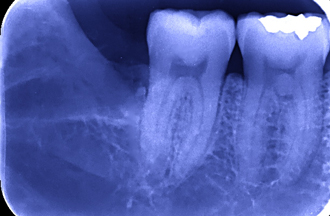

抜歯あとのレントゲン

コラム「抜歯あとのレントゲン」の画像